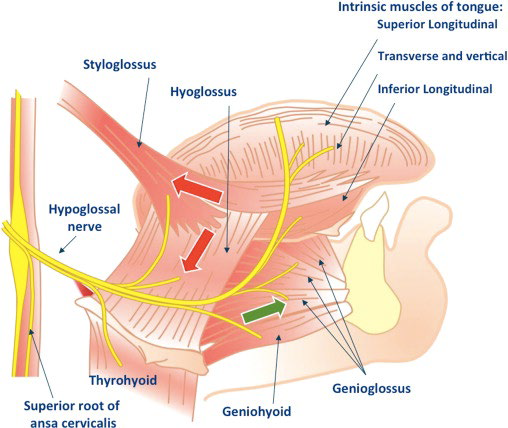

CN XII

- 跨過ECA所有分支,除了Occipital a.

- 與Ansa cervicalis 混和

- 支配舌部肌肉

Hyoglossus m. 外側

- Lingual n.

- Hypoglossal n.

- Submandibular duct

Extrinsic muscles

Motor:CN XII

移動舌頭

- Genioglossus(makes bulk of the tongue)

- Hyoglossus

- Styloglossus

Intrinsic muscles

Motor:CN XII

改變舌頭形狀

- Sup. longitudinal

- Inf. longitudinal

- Transverse

- Vertical